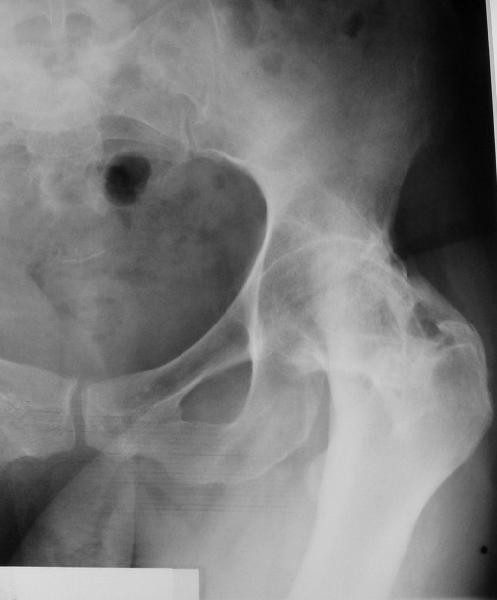

При обследовании выявлен анкилоз тазобедренного сустава в приведении. Видимо, в период пребывания в тяжелом состоянии появились гетеротопические оссификаты. За исключением того, что осталась одна почка, сейчас других медицинских проблем нет.

Пациентку в первую очередь беспокоят боли в спине, на отсутствие движений в суставе она вроде и не жалуется. Вопрос насчет тактики. Корсет и анальгетики вряд ли решение. Первый вариант - удаление оссификатов и эндпротезирование, второй - корригирующая остеотомия в проксимальном отделе с устранением порочного положения.

Второй вариант много проще и менее травматичен. Можно ли без размыкания сустава рассчитывать на существенное уменьшение боли за счет устранения перекоса таза?

Боли в спине обусловлены порочным положением бедра. Эндопротезирование более интересно, т.к. дает еще и движения в суставе (кроме устранения порочного положения). Оссификаты не страшные, а учитывая срок (3 года) - уже созревшие. Я зарекся делать ЭТС при больших оссификатах - очень частый рецидив даже на фоне индометацина и луч.терапии.

Я думаю, что эндопротезирование - более предпочтительный вариант у пациентки 53 лет. К тому же суставная щель прослеживается и, вероятнее, большой сложности с установкой вертлужного компонента не будет. Высока вероятность необходимости аддуктотомии.

Если есть, то операция на бедре не поможет. Если нет то есть вопрос - в каком положении контрактура?

В любом случае замена сустава после оссификации дело не благодарное - безболезненная контрактура станет болезненной контрактурой.

После корригирующей остеотомии сохранится чрезмерная нагрузка на поясничный отдел за счёт анкилоза т/бедр. сустава.На фоне остеохондроза,спондилёза,спондилоартроза и спондилолистеза устранение порочного положения не избавит от болей и вряд-ли даже уменьшит их.Мне кажется тут нет альтернативы эндопротезированию.Но даже в этом случае не исключено,что позднее, на повестке появится необходимость вмешательства на позвоночнике.